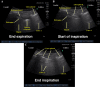

Hydro-Point in a ventilated COVID-19 patient with hydropneumothorax secondary to barotrauma